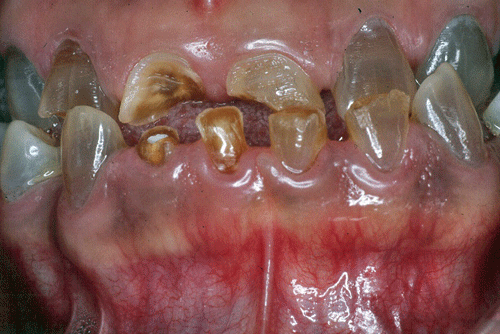

Extrabucalmente se observó una cara de forma triangular, con perdida de la dimensión vertical, colapsamiento de la expresión facial, pliegues mentolabial y nasolabial marcados y un perfil cóncavo. Al examen intrabucal los tejidos blandos tienen un aspecto normal; al de los tejidos duros se notó una coloración grisasea violeta generalizada de todos los dientes presentes, con diastemas, malposiciones múltiples y atrición que varía de grado leve a severo, en los dientes anteriores; dientes ausentes el 18, 16, 15, 14, 26, 27, 28, 37, 36, 46, y 47; mordida cruzada anterior y posterior; prognatismo mandibular; arcada superior de forma ovalada y asimétrica e inferior de forma ovalada y simétrica. (Fig. Nº2). En el análisis de la oclusión se evidencia la ausencia de relación molar y canina, en la palpación muscular y al examen de la articulación temporomandibular no se observó alteración.

Fig. Nº 2:

Vista intrabucal frontal del paciente con D.I. presentación inicial